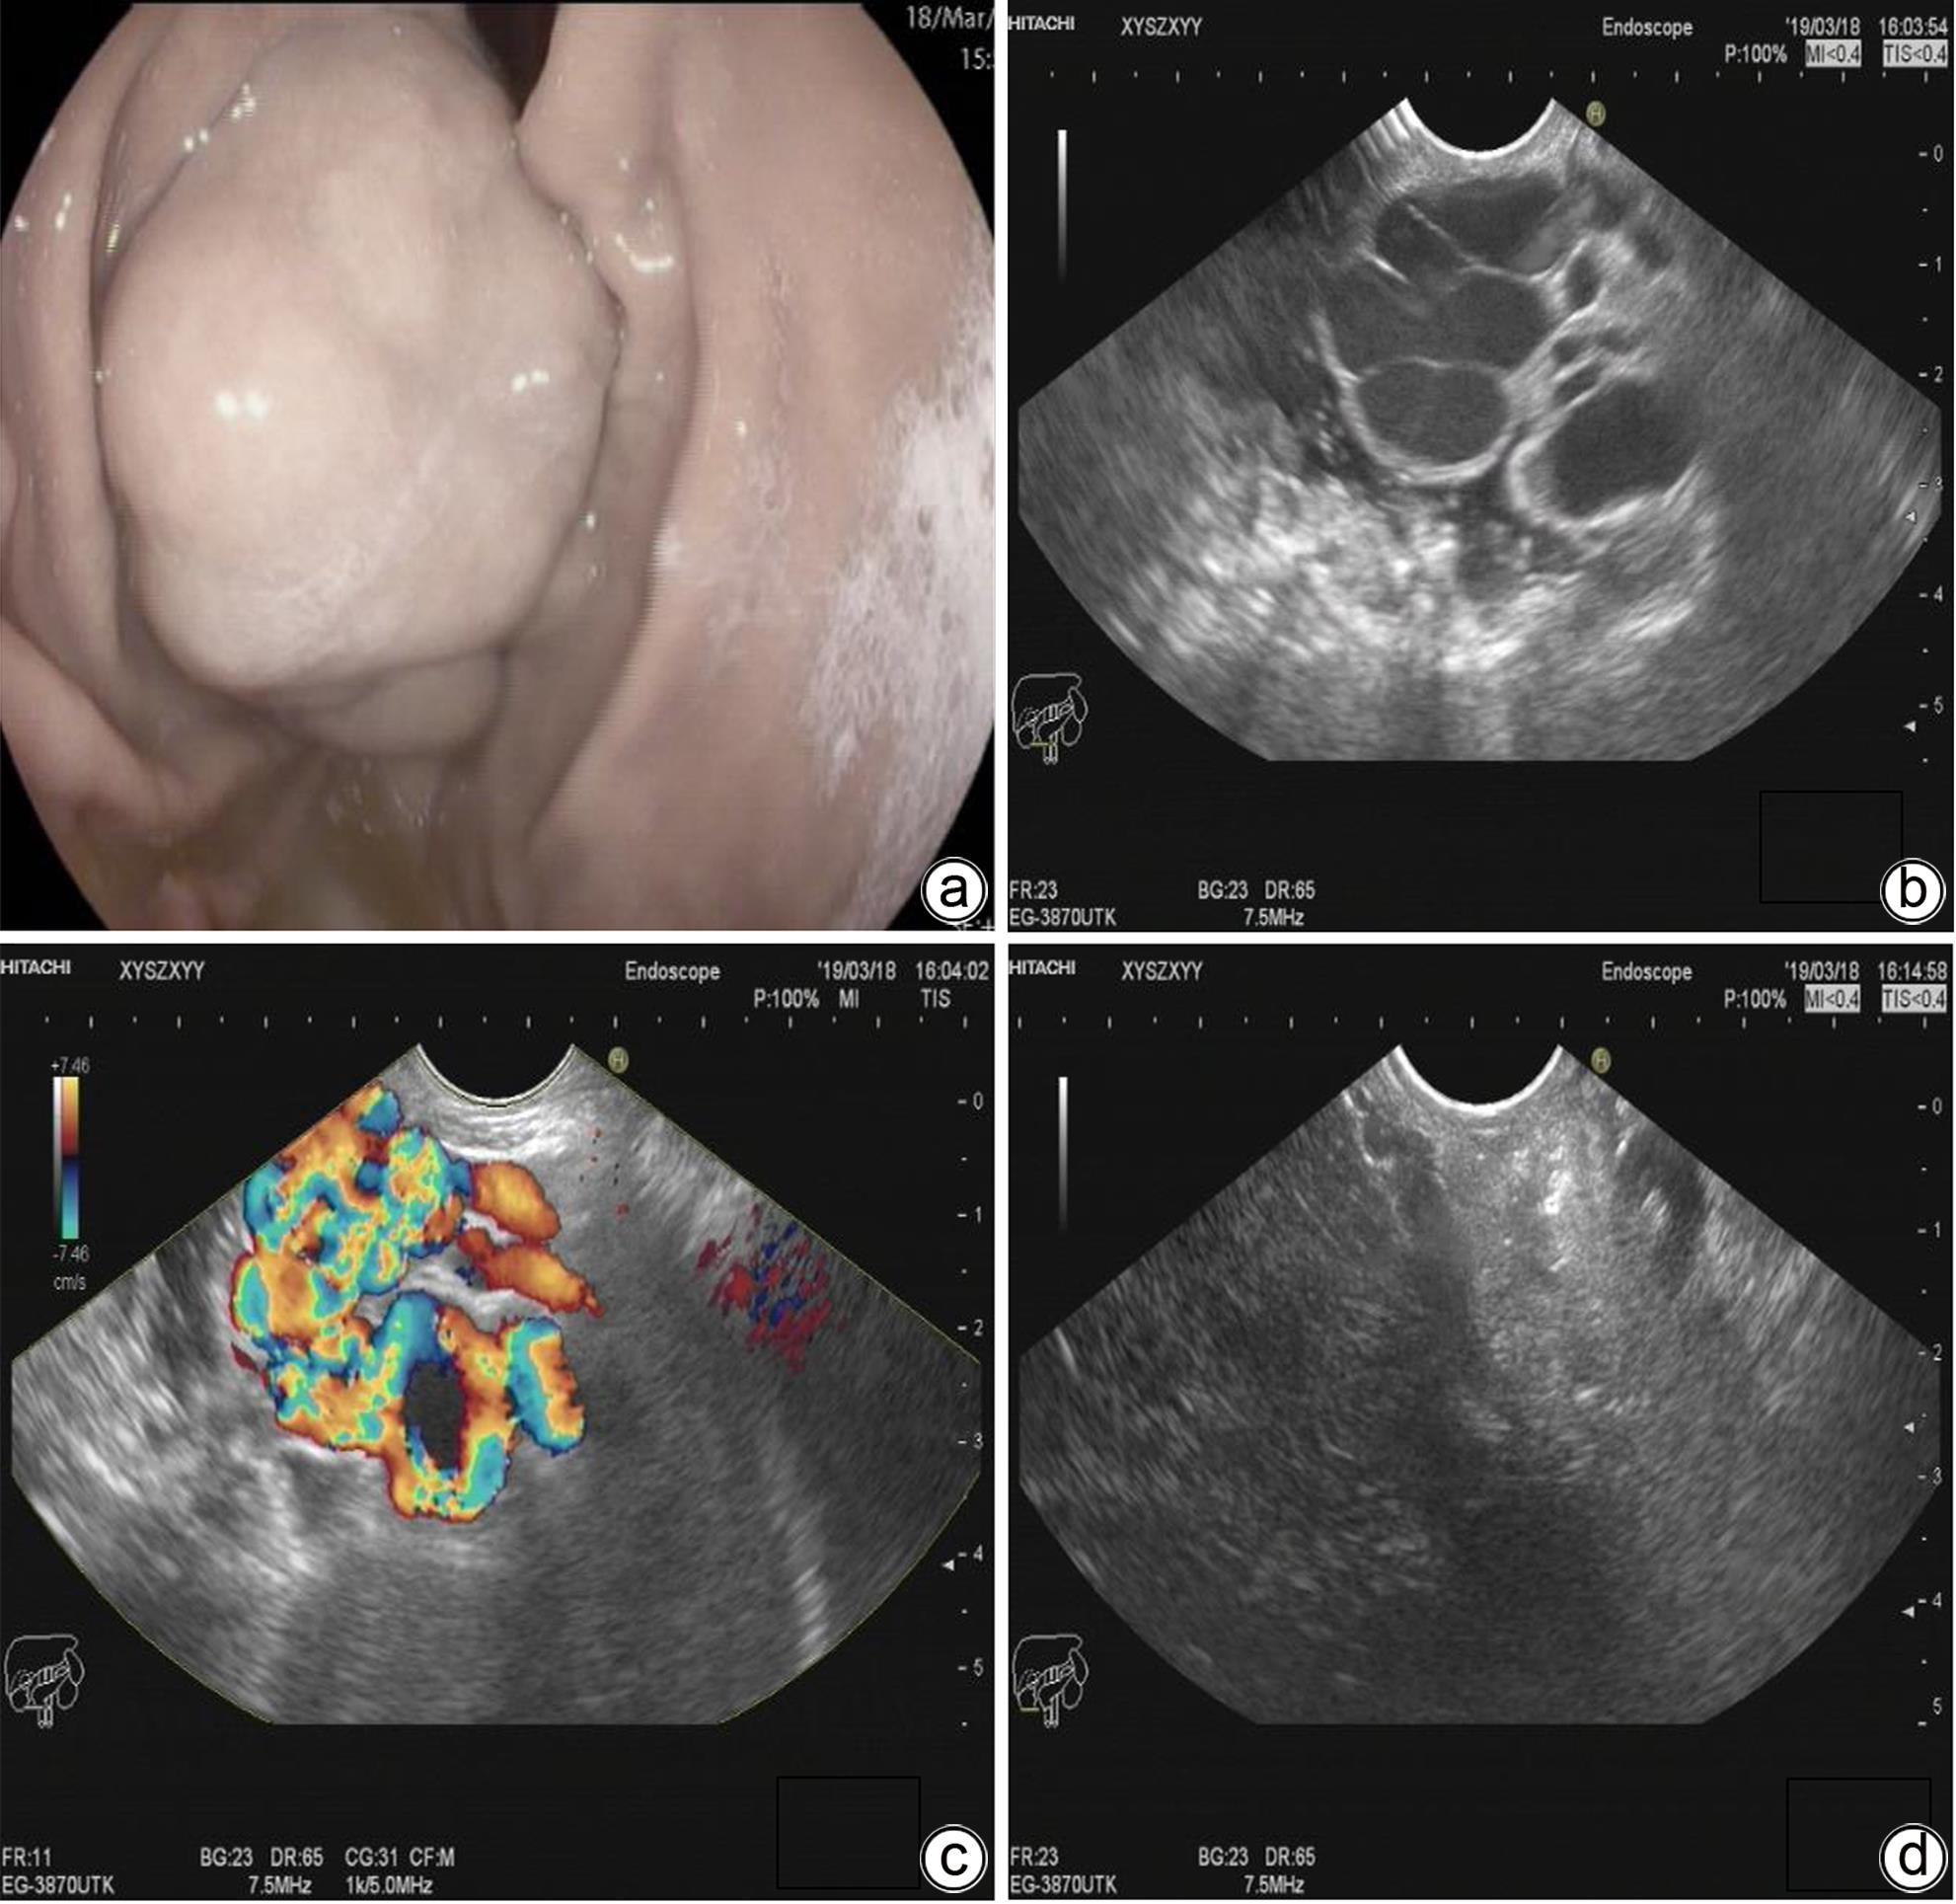

The preliminary therapeutic effect of endoscopic ultrasound-guided tissue adhesive injection with the assistance of metal clips in treatment of cirrhotic patients with gastric varices and gastric-renal shunt

Jiali MA, Zhenglin AI, Julong HU, Yu JIANG, Yuling ZHOU, Xiuxia LIANG, Hongshan WEI, Ping LI

2024, 40(4): 734-738. DOI: 10.12449/JCH240415

Abstract(1116) HTML (309) PDF (1036KB)(61)

Abstract:

Objective  To investigate the safety and efficacy of endoscopic ultrasound-guided tissue adhesive injection with the assistance of metal clips in the treatment of cirrhotic patients with gastric varices and gastric-renal shunt (GRS).  Methods  The patients who attended Beijing Ditan Hospital, Capital Medical University, due to liver cirrhosis and gastric varices from February to June 2023 were enrolled, and all patients were confirmed to have GRS and received endoscopic ultrasound-guided tissue adhesive injection with the assistance of metal clips. The primary evaluation index was alleviation or disappearance of varicose veins after surgery, and the secondary evaluation indices were surgical completion and complications.  Results  A total of 11 patients were enrolled in this study, among whom there were 7 male patients and 4 female patients, with a median age of 55 years. Of all patients, 1 had Child class A liver function, 7 had Child class B liver function, and 3 had Child class C liver function. The maximum (median) diameter of the shunt was 8 mm, and the minimum (median) diameter of the shunt was 4 mm. The median blood flow velocity of the target vessel was 11 cm/s before treatment and 5 cm/s after occlusion with metal clips. The median amount of tissue adhesive injected was 2 mL, and the amount of lauromacrogol used was 1 mL. Disappearance of blood flow signals was observed in all patients after surgery (100%), and the success rate of surgery was 100%. No patient experienced rebleeding after follow-up for 6 weeks. Gastroscopy at 1 month after surgery showed that gastric varices were eradicated or almost disappeared in 9 patients and were alleviated in 2 patients.  Conclusion  Endoscopic ultrasound-guided tissue adhesive injection with the assistance of metal clips is a feasible, safe, and effective treatment method for cirrhotic patients with gastric varices and GRS.